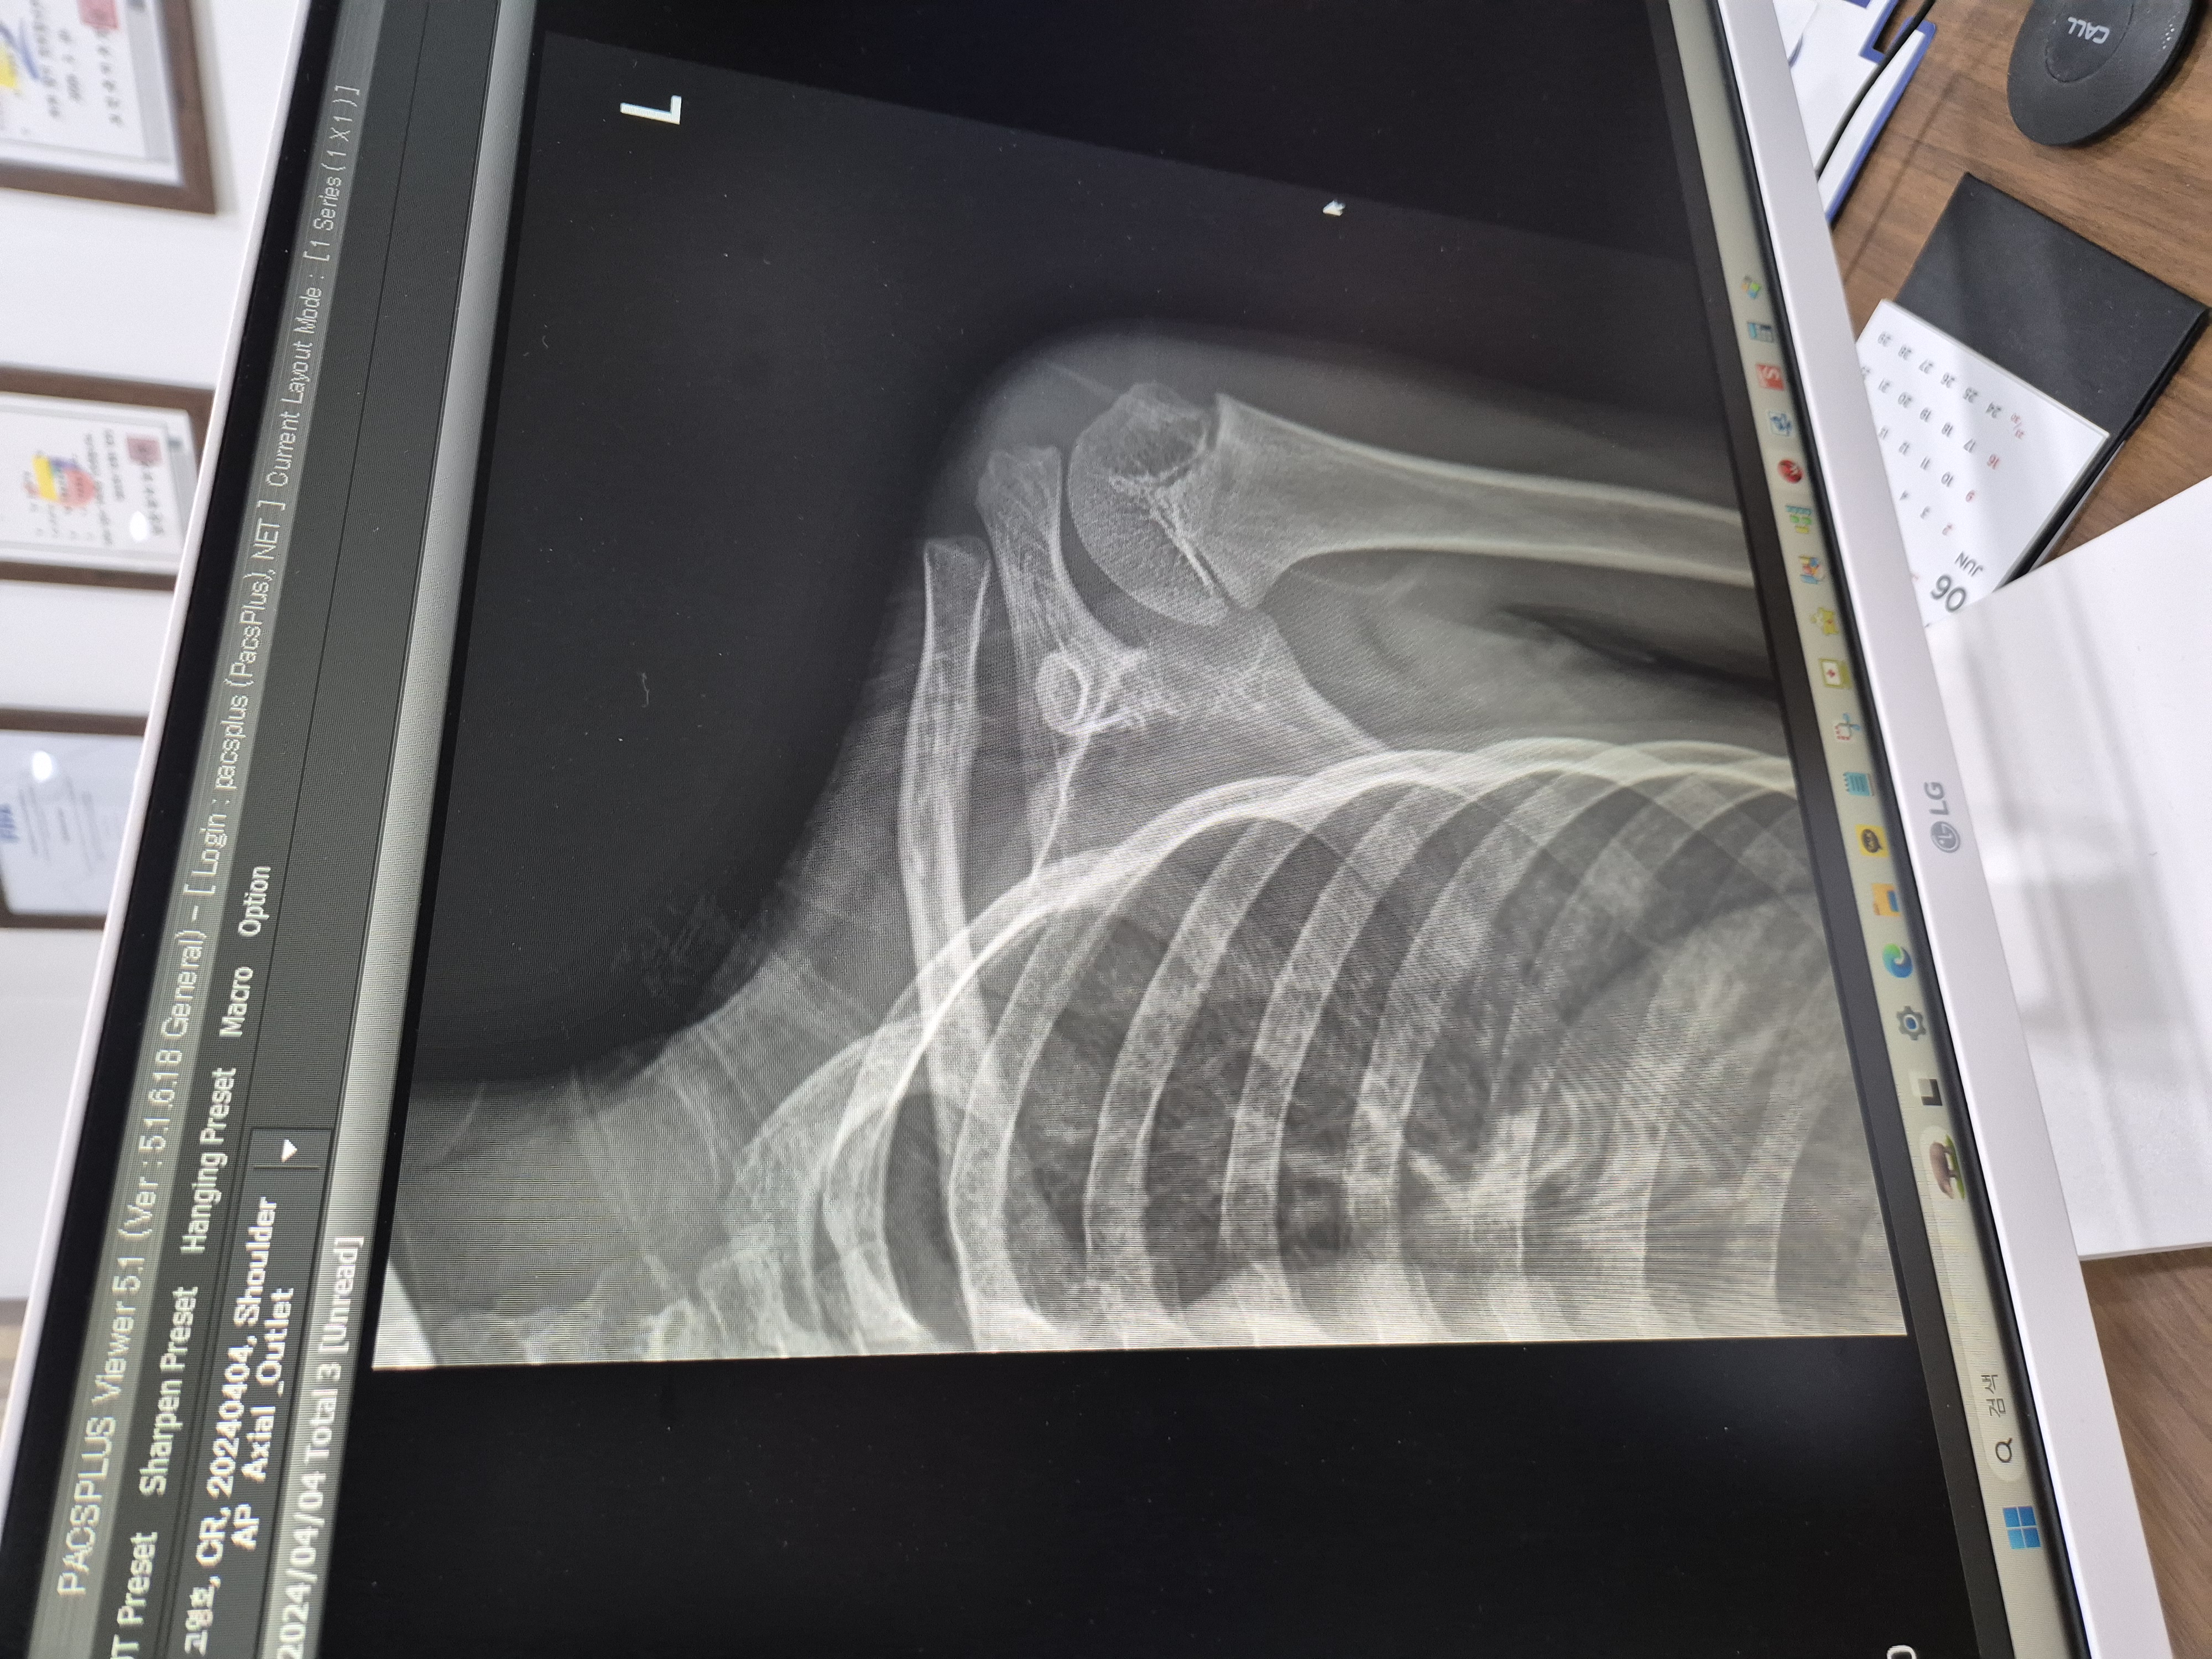

왼쪽이 부러진 쇄골 오른쪽이 정상 쇄골의 뼈모양이에요.

사진보면 완전히 어긋나있는데 부러졌을때 아이가 얼마나 아팠을까요ㅜㅜ

쇄골 부러지고 두달 지난 사진이에요.

부러진날 보면 뼈가 심하게 어긋나 있었는데 많이 내려온게 보이시죠? 저게 다 붙은거래요~

부러지기전 모양처럼 되려면 몇년 걸린다고 하더라고요.

그런데 아이 학교 건강검진때문에 다른 병원에서 엑스레이 찍었는데 부러진 뼈는 예전처럼 돌아오지 않을거라고 아마도 평생 쇄골 모양이 저럴꺼라고 하더라고요.